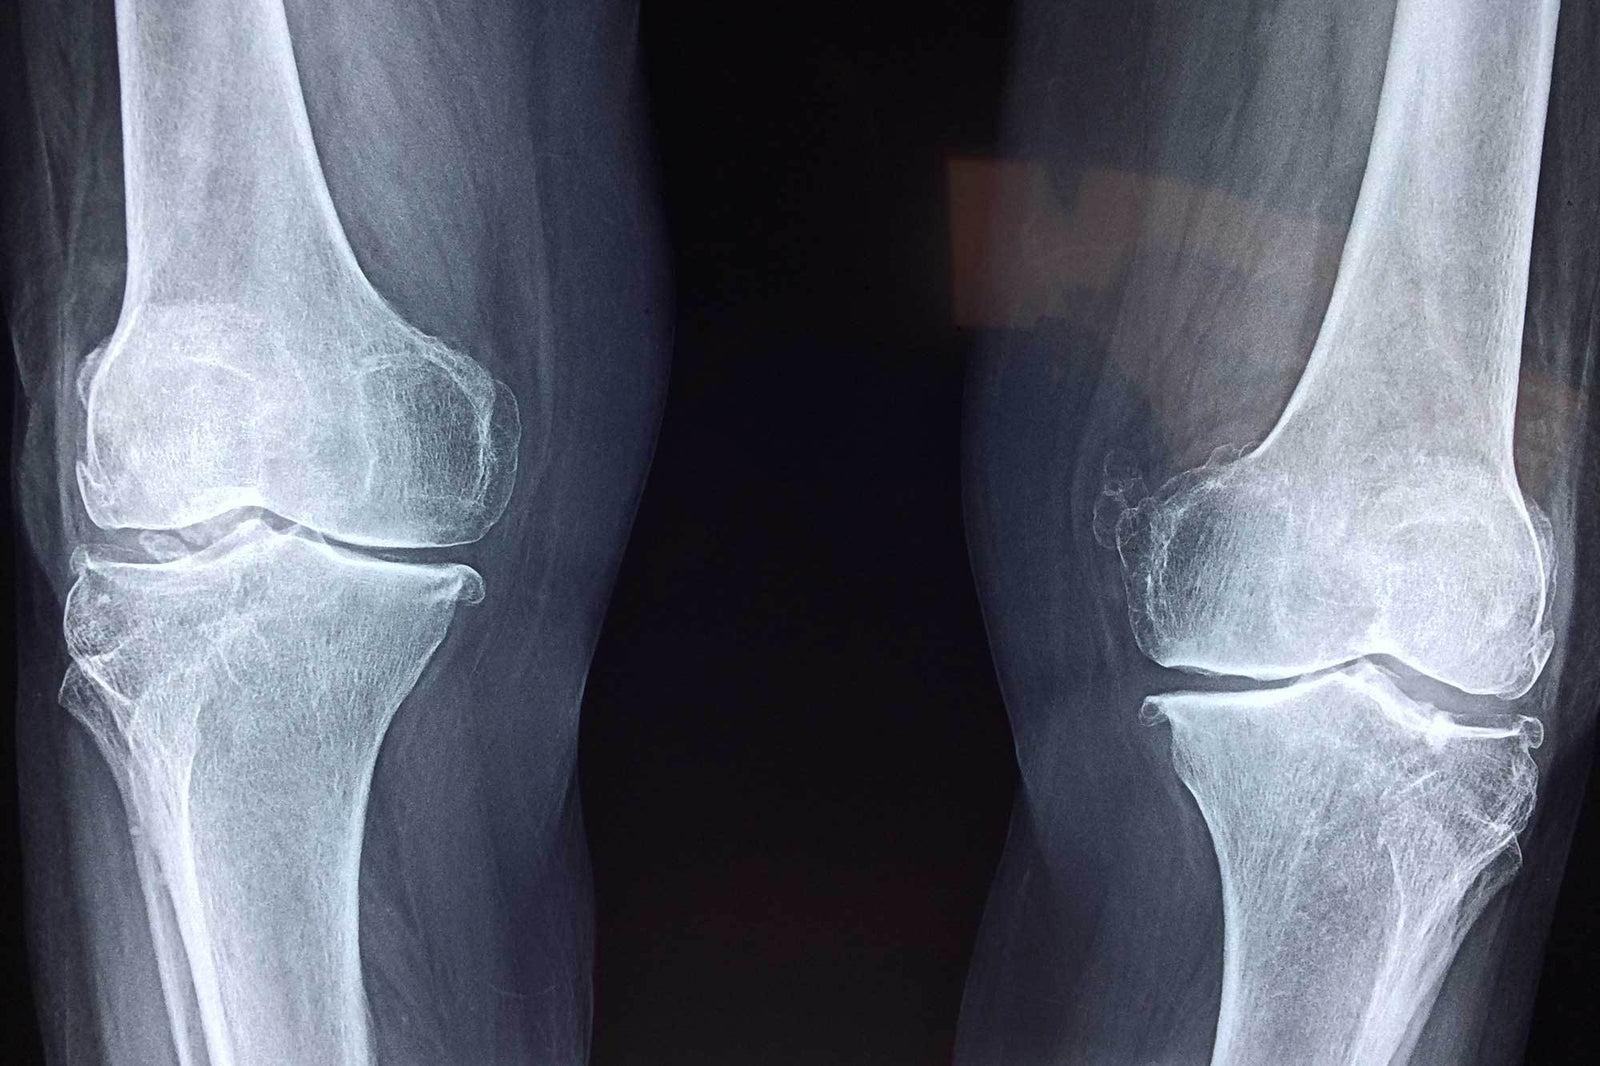

Did you tear a meniscus recently? You are not alone. Meniscus tears are a very common injury in sports. The states that there are over 200,000 cases of a torn meniscus each year in the United States. Your meniscus is a rubbery cartilage situated between your shin bone and your thigh bone which acts like a cushion. The meniscus can tear with forceful twisting or rotation of the knee, movements that are common to sports. A torn meniscus will cause pain, swelling and may prevent you from fully extending your knee.